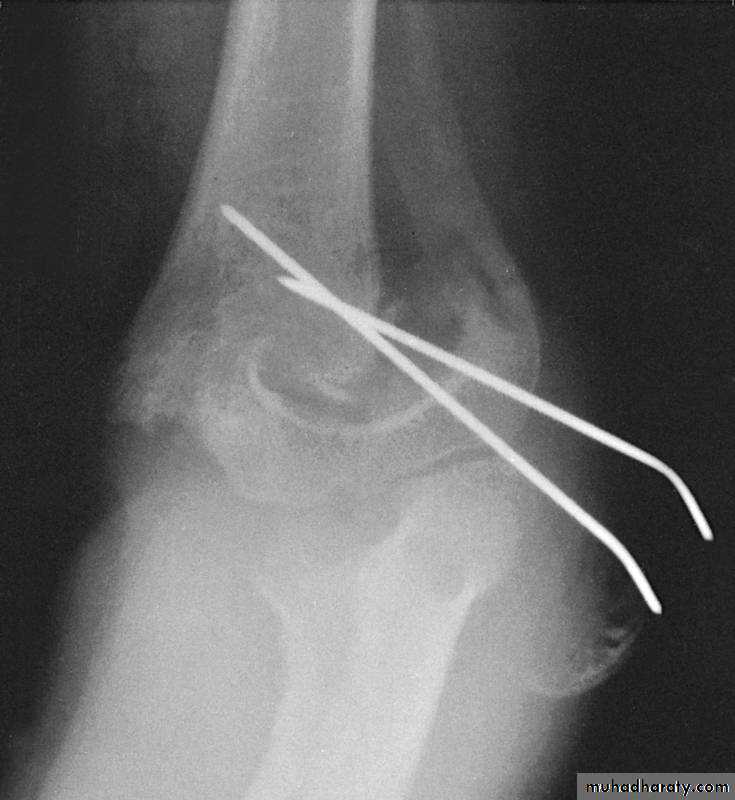

Percutaneous

pin

fixation

If a cast is inadequate,

then what is the standard for maintaining the reduction?

Medial-lateral

pins

In what manner may the pins be used?

Two lateral

pinsPins crossing at the

fracture lack stability

*Cheng J, Lam T, Shen W.

J Orthop Trauma 9:511,1995.

What are the principles of lateral pin fixation?